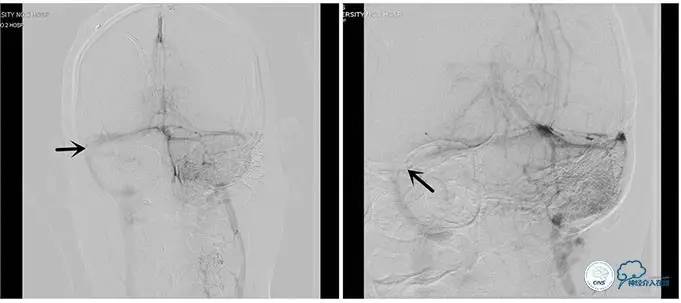

术中右侧ICA造影

右侧ICA斜位及窦内造影

右侧ICA斜位

窦内造影及路图

术中测压:

远端:520mmH2O,

近端:190mmH2O。